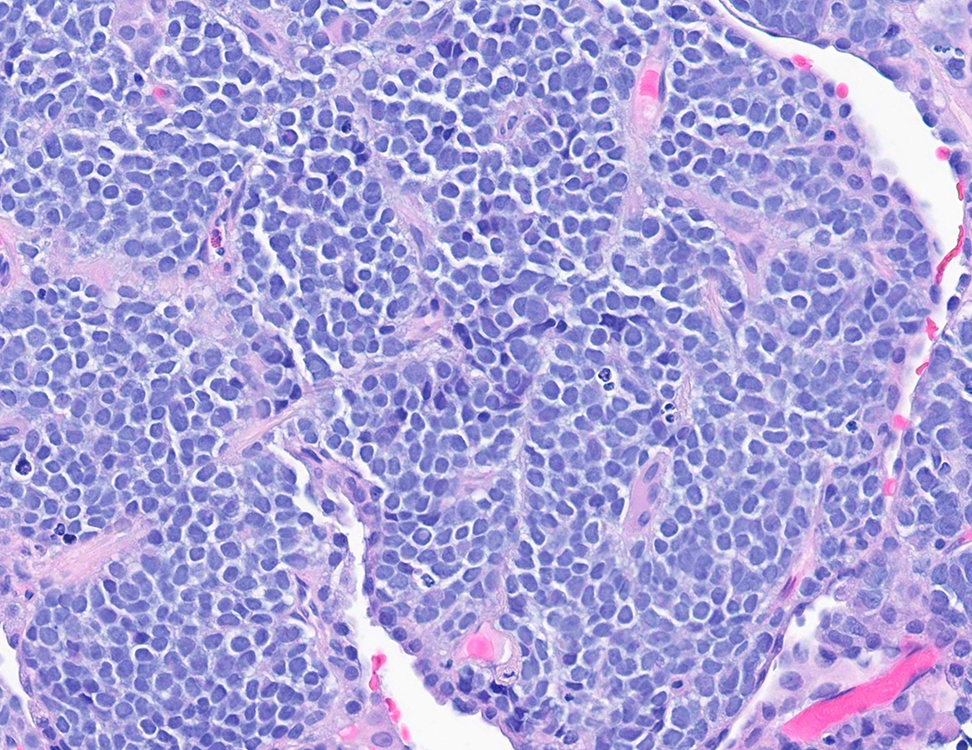

Figure 3 (H and E 40x)